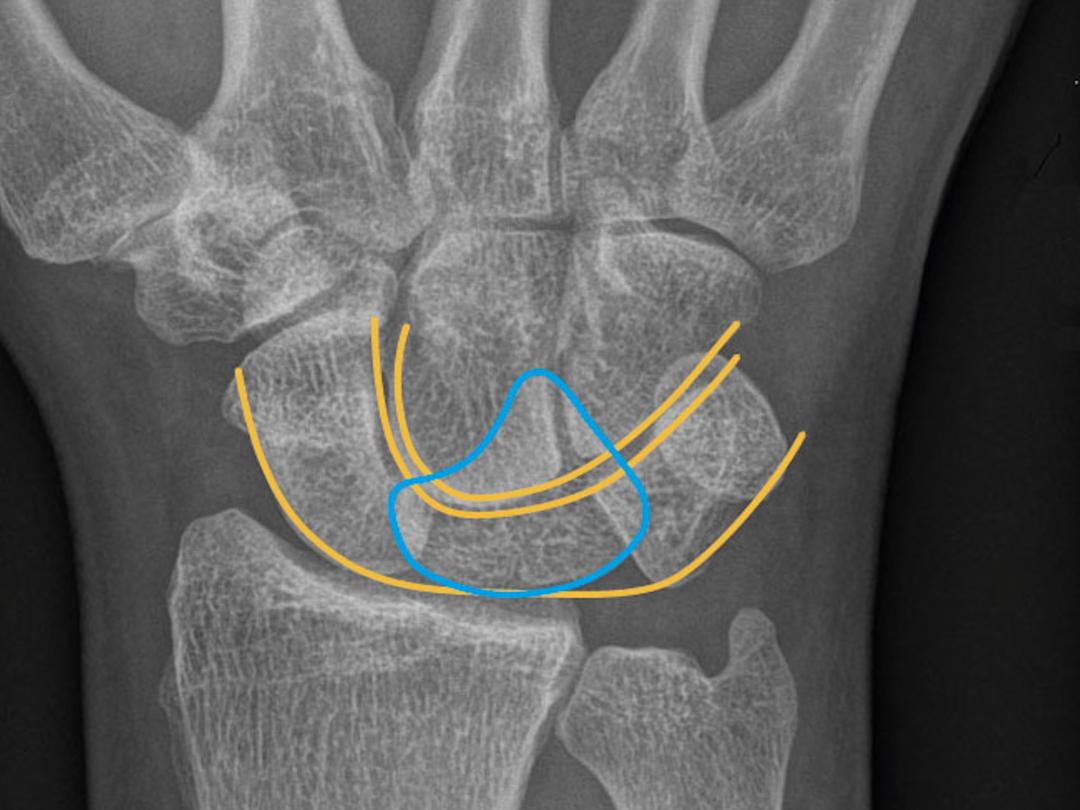

Röntgenfoto van de pols.

Een 57-jarige man werd 5 dagen na een val van de fiets door de huisarts verwezen naar de SEH vanwege aanhoudende, progressieve pijn van de rechter pols. Direct na de val had patiënt de huisartsenpost bezocht, alwaar de diagnose ‘distorsie’ was gesteld. Bij lichamelijk onderzoek zagen wij zwelling van de pols aan de volaire zijde. Patiënt kon de pols beperkt bewegen en ervoer drukpijn aan de volaire zijde. Ook was er sprake van pijn en tintelingen in de duim, wijsvinger en middelvinger en aan de mediale zijde van de ringvinger, passend bij compressie van de N. medianus. Op de…